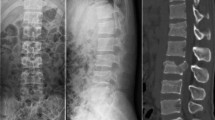

Combined posterior–anterior stabilization using an expandable vertebral body replacement device (VBRD) for anterior column reconstruction (ACR) has been advocated and successfully used by several authors for unstable thoracolumbar burst fractures with significant vertebral body comminution [1,2,3,4,5,6,7,8]. This approach allows for posterior reduction and stabilization (with or without neural decompression) as well as for immediate restoration of the structural strength and load-bearing capacity of the anterior column; it offers high primary biomechanical stability [9,10,11,12,13] and is associated with only minimal postoperative loss of kyphosis correction [1,2,3,4]. Typically, the VBRD is placed bisegmentally between the superior endplate of the caudad intact vertebra and the inferior endplate of the cephalad intact vertebra (bisegmental ACR, Fig. 1a). This results in fusion of two motion segments and requires partial resection of the fractured vertebral body (including the superior and inferior endplate) as well as of the adjacent cephalad and caudad intervertebral discs.

Anterior column reconstruction (ACR) using a vertebral body replacement device (VBRD). In bisegmental ACR (a), the VBRD is placed bisegmentally between the superior endplate of the caudad intact vertebra and the inferior endplate of the cephalad intact vertebra. In monosegmental ACR (b), the VBDR is placed monosegmentally between the inferior endplate of the fractured vertebra and the inferior endplate of the cephalad intact vertebra

In a substantial portion of burst fractures with significant vertebral body comminution, however, the inferior endplate is intact or shows a simple split fracture line only. In this situation, the VBRD may be sufficiently anchored in the intact caudal part of the fractured vertebra and thus may be implanted monosegmentally between the inferior endplate of the fractured vertebra and the inferior endplate of the cephalad intact vertebra (monosegmental ACR, Fig. 1b). As opposed to bisegmental ACR, monosegmental ACR offers the advantages of (1) sparing one spinal motion segment in these predominantly young patients and of (2) reducing the distance for osseous bridging to achieve bony fusion. However, there are no studies to date that have systematically assessed the feasibility and outcome of monosegmental ACR using a VBRD in thoracolumbar burst fractures.

All study patients underwent combined posterior–anterior stabilization with thoracoscopic anterior column reconstruction using an expandable VBRD as described by Knop et al. [16]. Overall the procedure was carried out as a one-staged procedure in 26 patients and as a two-stage procedure in 11 patients (Table 2). In a first step, posterior reduction and bisegmental posterior instrumentation using an angular stable pedicle screw system including a crosslink (USS™ pedicle screw System, Synthes Medical, Oberdorf, Switzerland) was performed with the patient in the prone position. In a second step, the anterior column was reconstructed via four standardized portals with the patient in a right lateral decubitus position and with one-lung ventilation. For monosegmental anterior column reconstruction, the VBRD was monosegmentally implanted and expanded between the inferior endplate of the fractured vertebra and the inferior endplate of the cephalad intact vertebra (Fig. 1b). For bisegmental anterior column reconstruction, the VBRD was bisegmentally implanted and expanded between the superior endplate of the caudad intact vertebra and the inferior endplate of the cephalad intact vertebra (Fig. 1a).